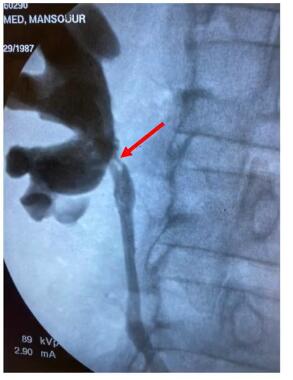

顺行和逆行

输尿管肾盂造影:

肾盂输尿管连接处造影剂完全停止完全进入肾盂,输尿管上段缺损